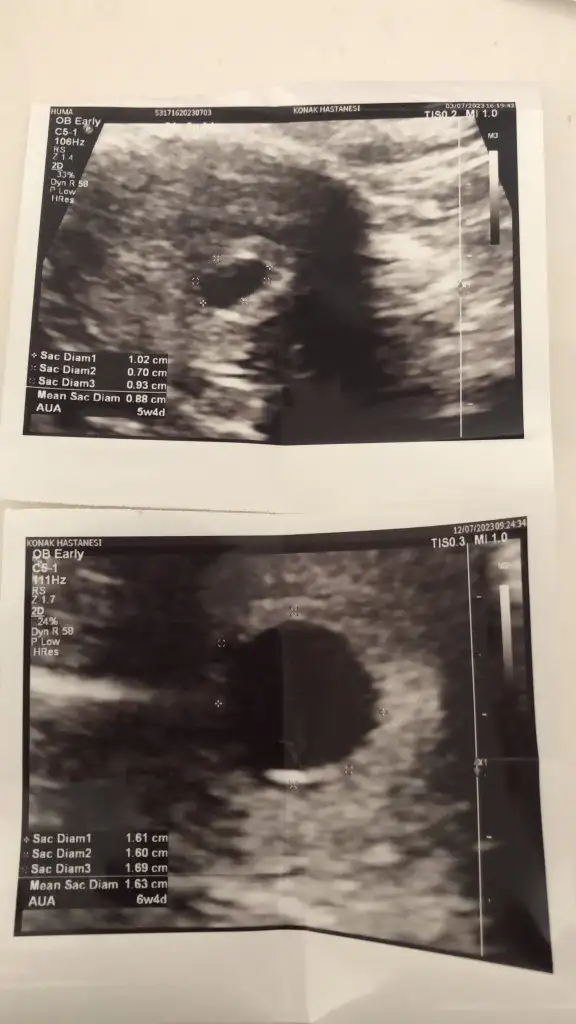

htimal umutlanıyor insan belki görünür diye kese büyümüş ama maalesef bebek yok içindeİkinci fotoğraf tam daire gibi hiç böyle görmemiştim genelde yumurta şeklinde oluyor hep, boş gebelik olabilir yolk da görünmüyor

Canım bi arkadasımın 8. Haftada göründü onada boş gebelik demişti o bekledi bebek göründü ama bende öyle olmadı malesef 8 haftayı gecmıstım yınede yoktu mecbur kürtaj oldum inşallah senin görünürKızlar selam ben 5+4 ken keseyi gördüm doktor bir hafta sonra gel dedi ama geç döllenme olduğunu söyledi 6+4 ken gene kese var ama bebek yok alltan muayene de de gözükmedi pazartesi günü tekrar çağırdı boş gebelik kürtaj gerekli dedi. Bu durumu yaşayan varmı bebek sonra dan görünür mü lütfen yardımcı olabilir misiniz

Yuvarlak kese boş gebelik diyorlarKızlar selam ben 5+4 ken keseyi gördüm doktor bir hafta sonra gel dedi ama geç döllenme olduğunu söyledi 6+4 ken gene kese var ama bebek yok alltan muayene de de gözükmedi pazartesi günü tekrar çağırdı boş gebelik kürtaj gerekli dedi. Bu durumu yaşayan varmı bebek sonra dan görünür mü lütfen yardımcı olabilir misiniz